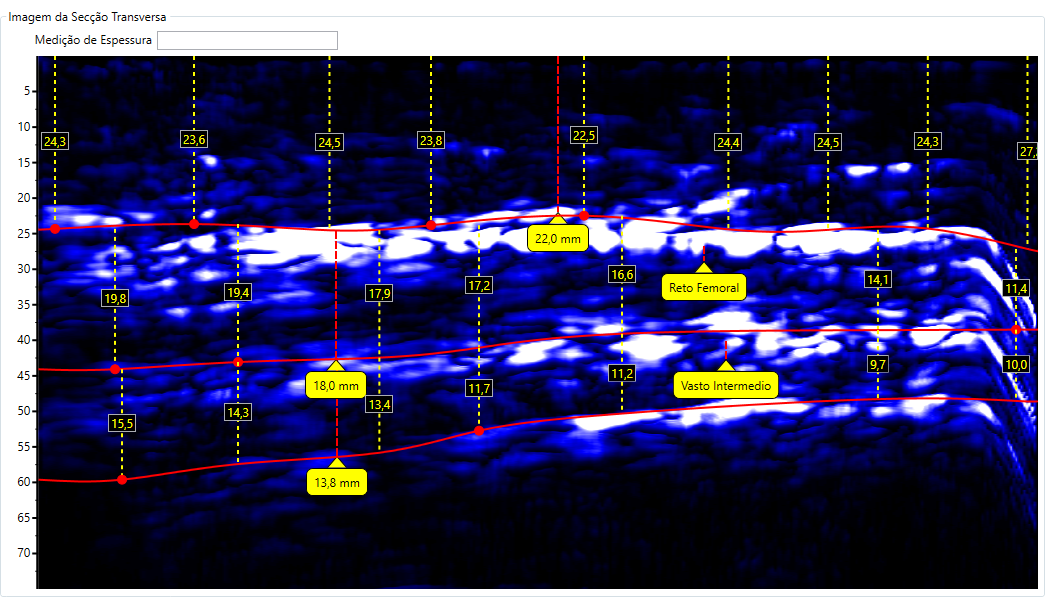

Escaneamento da Coxa